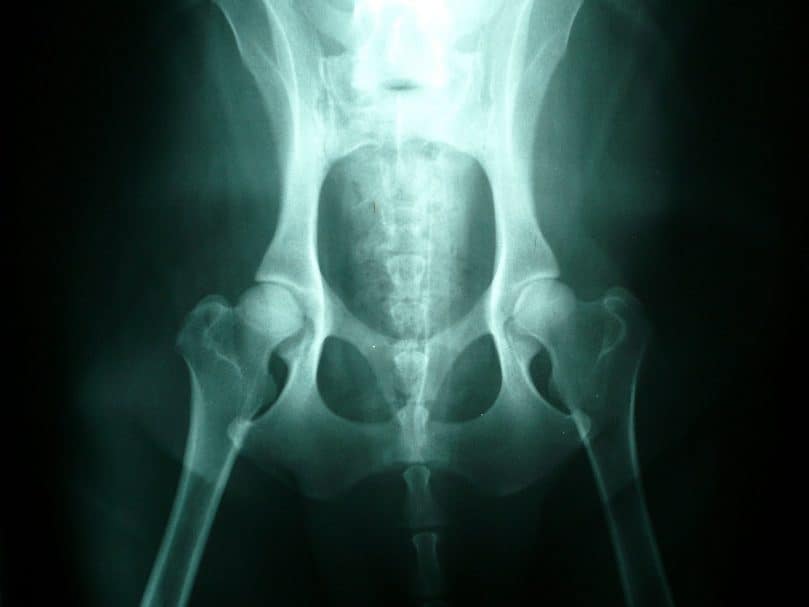

Dùng X quang có thể phát hiện bệnh sớm và biết được xương xốp, ranh giới giữa cốt mạc và tổ chức cốt mạc dây, khớp xương sưng to, có khi có u xương.